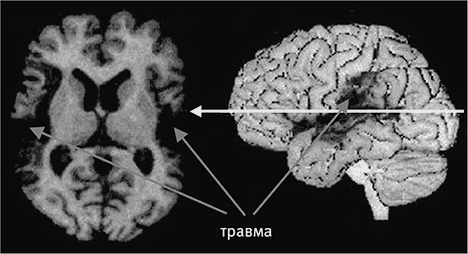

Рис. п.3. Пример МРТ-скана, позволяющего выявить повреждение мозга

Этот пациент перенес два инсульта подряд, в результате чего у него разрушились слуховые зоны коры правого и левого полушарий. Травма хорошо видна на изображении, полученном методом МРТ.